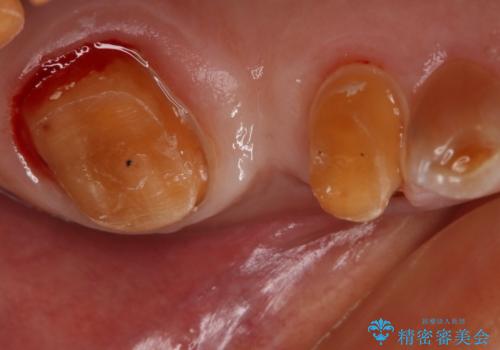

- 左上臼歯部に保険のブリッジを入れていたがすぐに取れてしまったので自費治療でのやり変えを希望された患者様です。

インプラントとブリッジを提案しましたが時間をかけたくないとのことだったので、ブリッジでの治療を選択しました。

左上6番が大きく傾いているため、露髄や痛みが出る可能性を事前にお伝えしています。